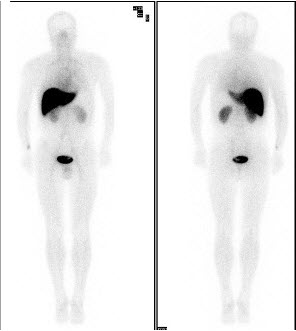

49、多项选择题

男,37岁,诉全身多处骨关节疼痛,夜间尤甚,无发热。行Tc-MDP骨断层显像如图。对此影像地描述正确的是()

A.胸7含放射性“冷区”

B.胸8含放射性“冷区”

C.下位胸椎放射性增浓是正常的

D.腰3附件异常浓聚

E.胸7、胸8、腰5骨转移瘤可能性大

点击查看答案